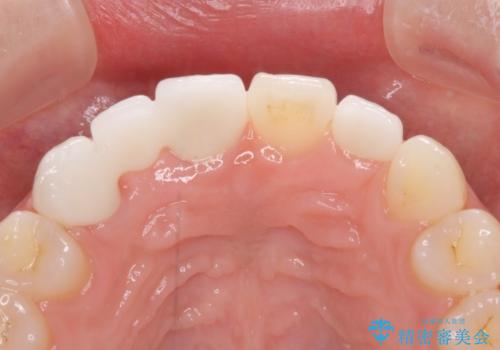

欠損歯と矮小歯 矯正治療と前歯のセラミック治療

診察の結果、前歯が1本欠損しており、さらに矮小歯(通常よりも小さい歯)が1本存在していました。

矯正治療後には欠損部はオールセラミックブリッジに、矮小歯はオールセラミッククラウンにて補綴することとしました。

前歯のスペースは、堅い線維の通った歯肉があり、幅も大きかったことから、歯肉切除を行った上でワイヤー矯正により移動を行いました。また、上唇小帯も歯間部付近まで付着していたため、合わせて切除しました。